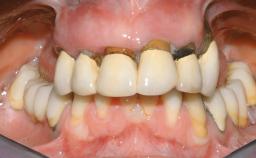

Immediate Loading of Six Implants in the Maxilla and Final Restoration with a Full-Arch CAD/CAM Zirconia FDP

A 63-year-old male patient was referred for a consultation and treatment of partial edentulism in the maxilla. The patient presented with residual anterior teeth and declined a partial removable prosthesis. He reported that the maxillary posterior teeth had been extracted due to mobility and periodontal disease two months before the consultation. The patient’s chief complaint was that his residual maxillary teeth were mobile and that he was unable to chew. The patient’s desire was a stable and comfortable fixed maxillary rehabilitation. The patient was a light smoker (fewer than 10 cigarettes/ day), and his medical history was without significant findings. He was not on any regular medication at the time of consultation. The extraoral examination revealed a normal physiognomy with a correct distribution of the facial thirds. The patient presented a low lip line, and the transition line between teeth and soft tissues was not exposed during a forced smile.

Defining Characteristics Fully edentulous upper jaw to be rehabilitated with an implant-borne fixed dental prosthesis

Loading Protocol Immediate

Provisional Implant-Supported Prosthesis Prosthodontic margin < 3 mm apical to mucosal crest Prosthodontic margin < 3 mm apical to mucosal crest